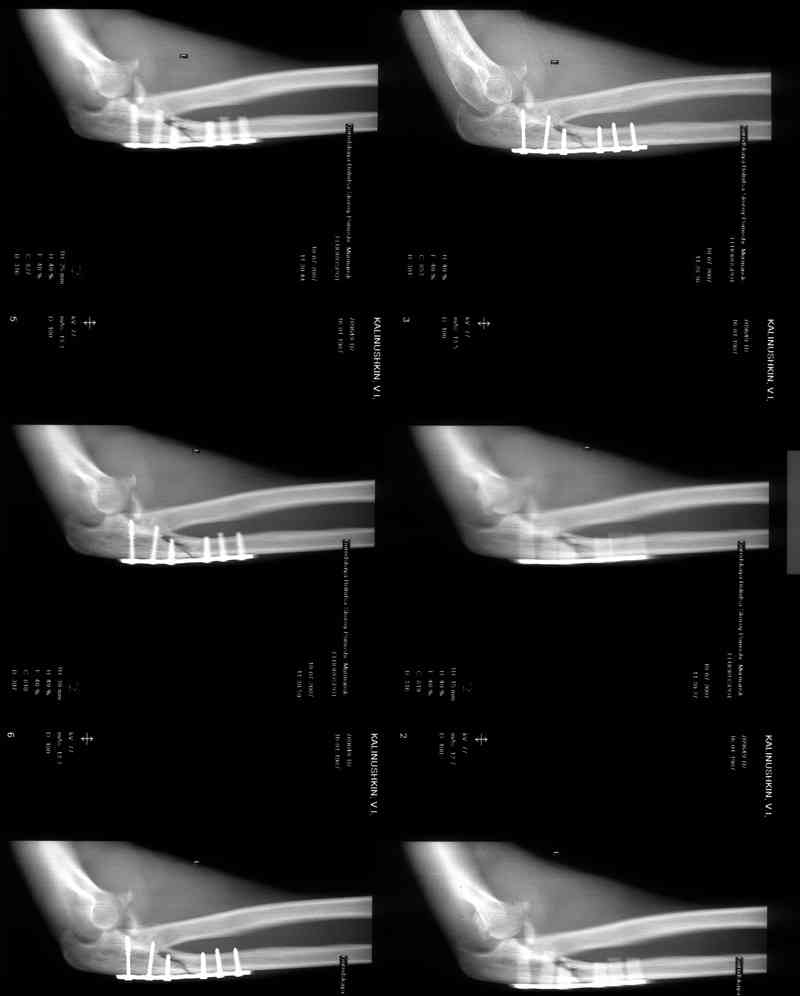

Re: Несросшийся перелом локтевой кости, подвывих предплечья кзади.Перелом венечного отростка. Состояние после резекции головки лучевой. Травма 4 мес. назад.

Больной наблюдался в поликлинике,к нам попал

через 3 мес. Отмечается контрактура локтевого сустава, сгибание/разгибание 30/0/0.

МРТ у нас нет, сделаны томограммы.